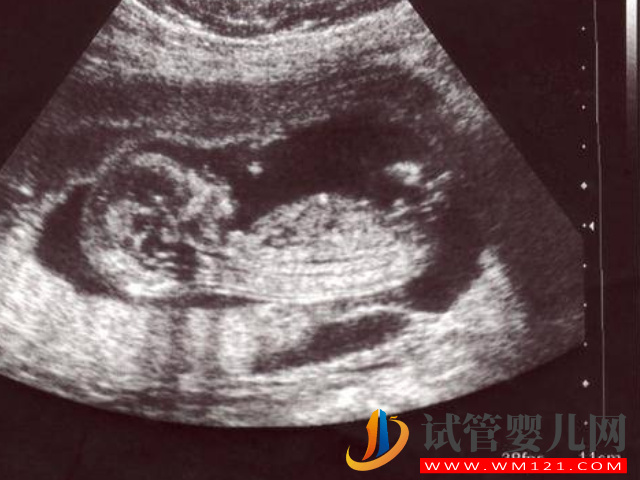

- 4. 也可以看在做四維彩超的時(shí)候看圖像,如果你看到在本部下半身的地方有三條白線的話,可能就是女孩,如果沒有看到明顯的三條白線,就看兩腿之間有沒有突出的東東,且中間有小凹槽的,也代表是個(gè)女孩。男孩的話一般下半身是有圓圓凸出的東西,這個(gè)可能就是他們的生殖器官;

- 5. 而且在做四維彩超的時(shí)候可以監(jiān)測(cè)到孕囊形狀的,如果孕囊是形狀像茄子和長條狀的話,那么就是男孩,如果孕囊是橢圓形或圓形的,就是女孩;